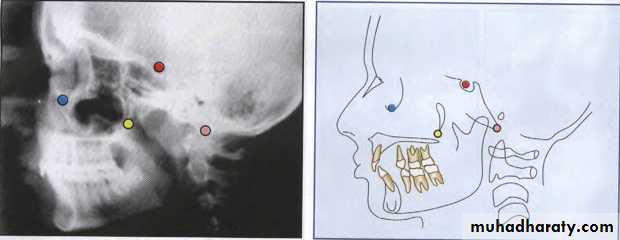

-- JacobsonLandmarks

This is a 11 factor summary analysis that employs specific measurements toLocate the chin in space

Locate the maxilla through the convexity of the faceLocate the denture in the face

Evaluate the profile

This analysis employs somewhat less traditional measurements & reference points

En = nose

DT = soft tissue

Ti = Ti point

Po = Cephalometric

Gn = Gnathion

A6 = upper molar

B6 = Lower molar

Go = gonion

C1 = condyle

DC=articular

CC = Center of cranium

CF = Points from planes at pterygoid

Xi point

A point located at the geometric center of the ramus. Location of Xi is keys of geometrically to Po-Or (FH) and perpendicular through Pt (pterygoid vertical [PtV]; aline perpendicular to FH at the posterior margin of the pterygopalatine fossa) in the following steps:1. Planes perpendicular to FH and PtV are constructed.

2.The constructed planes are tangent to points R1, R2, R3, and R4 on the borders of the ramus.3.The constructed planes form rectangular enclosing the ramus.

4. Xi is located in the center of the rectangle at the intersection of the diagonals.

Xi point --

Rl·mand. The deepest point on the curve of the anterior border of the ramus, one half the distance between the inferior and superior curves.

R2- mand. Apoint located on the posterior border of the ramus of the mandible.

R3-mand. Apoint located at the center and most inferior aspect of the sigmoid notch of the ramus of the mandible.R4-mand. Apoint on the lower border of the mandible, directly inferior to the center of the sigmoid notch of the ramus.